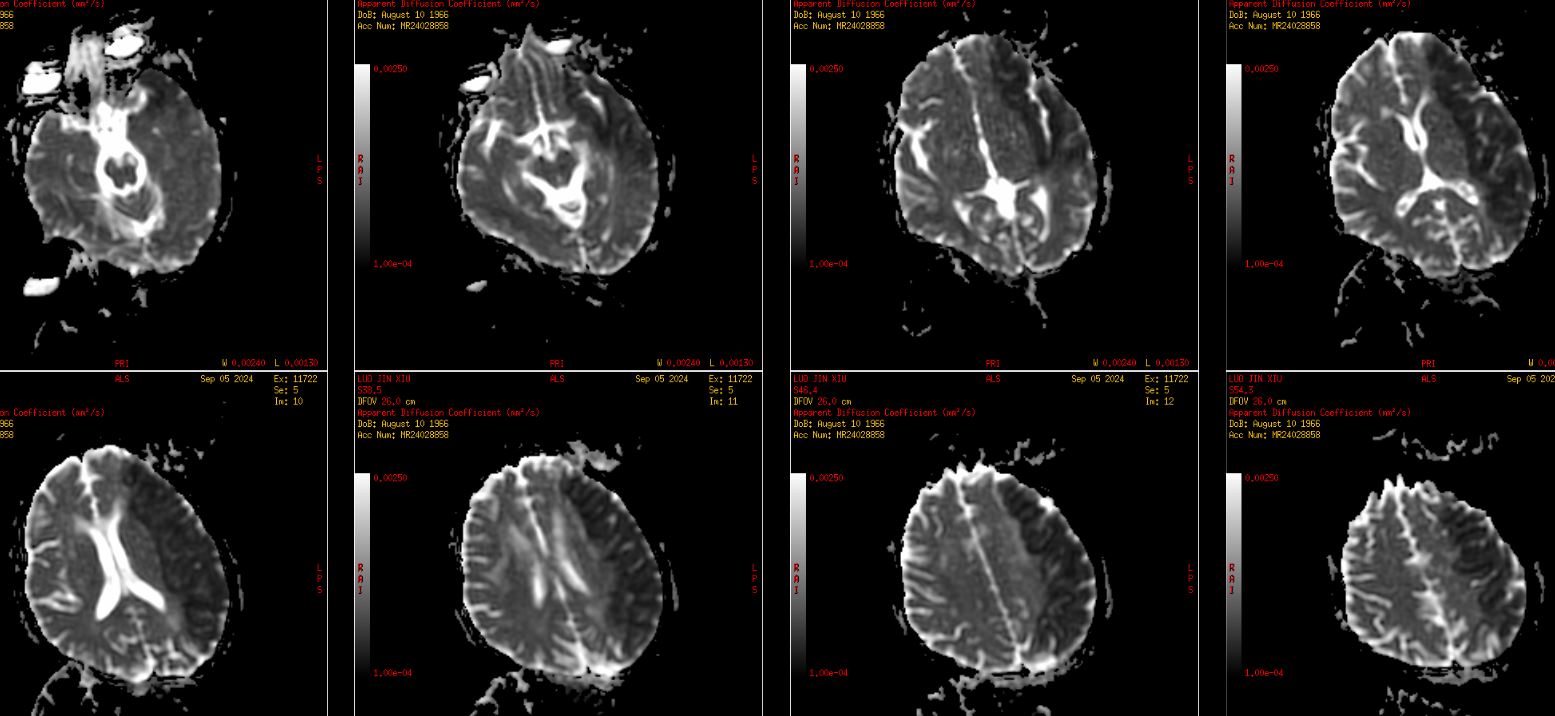

虽CTA提示颅内段颈内动脉及左侧颈内动脉颅内分支无明显缺失,但大脑中动脉远端分支明显稀疏,显影不佳。再结合头颅磁共振了解代谢情况。

术后当天麻醉苏醒顺利,右侧肢体活动较术前好转,能抬离床面,考虑大面积脑梗死,术后予单抗、他汀、清除自由基等治疗。

复查CT无出血,无造影剂外渗,病灶范围较大,侧脑室受压,适当脱水,控制颅内压,考虑大面积梗死,又是ICAS,选择使用单抗。

此次复查患者颅内水中完全消退,片中所示低密度灶范围较术前明显减少,结合患者症状表现,患者明显获益。